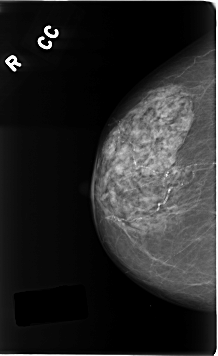

ics_version 1.0 filename C-0196-1 DATE_OF_STUDY 16 9 1996 PATIENT_AGE 83 FILM FILM_TYPE REGULAR DENSITY 2 DATE_DIGITIZED 26 3 1998 DIGITIZER LUMISYS LASER SEQUENCE LEFT_CC LINES 4728 PIXELS_PER_LINE 2536 BITS_PER_PIXEL 12 RESOLUTION 50 OVERLAY LEFT_MLO LINES 4736 PIXELS_PER_LINE 2712 BITS_PER_PIXEL 12 RESOLUTION 50 OVERLAY RIGHT_CC LINES 4616 PIXELS_PER_LINE 2824 BITS_PER_PIXEL 12 RESOLUTION 50 NON_OVERLAY RIGHT_MLO LINES 4672 PIXELS_PER_LINE 2712 BITS_PER_PIXEL 12 RESOLUTION 50 NON_OVERLAY |

FILE: C_0196_1.LEFT_CC.OVERLAY TOTAL_ABNORMALITIES 1 ABNORMALITY 1 LESION_TYPE MASS SHAPE OVAL MARGINS SPICULATED ASSESSMENT 5 SUBTLETY 5 PATHOLOGY MALIGNANT TOTAL_OUTLINES 1 BOUNDARY |